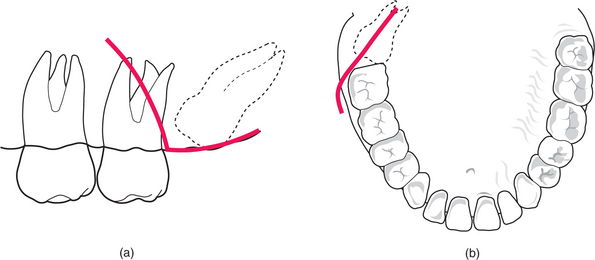

One simple method of determining the type of impaction involves comparing the distance between the roots of the third and second molar (a) with the distance between the roots of the second and first molars (b) (Fig. 5.11). If (a) is greater than (b) it is a mesioangular impaction; where (a) is less than (b) it is a distoangular impaction; where (a) is equal to (b) it is a vertical impaction. If the first molar is missing, the impaction can be determined by comparing a line drawn down the long axis of both the second and third molars: if parallel, it is vertical; if lower 8 leans towards lower 7 it is mesioangular; if the lower 8 long axis diverges from that of the 7, then it is a distoangular impaction.

image

Fig. 5.11 The author’s method to determine the type of impaction of a third molar by reference to spacing between the roots of the molar teeth. See text for details.